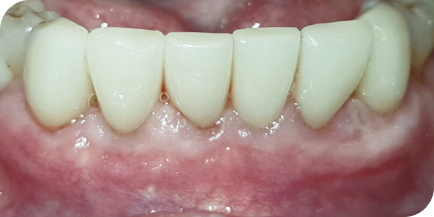

Пациентка (Ольга, 38 лет) обратилась в нашу клинику с жалобами на боль в дёснах, подвижность зубов, неприятный запах изо рта.

Мы провели полную диагностику. Диагноз — хронический генерализованный пародонтит средней степени тяжести. Выявлены проблемы: подвижность зубов 1-й степени, пародонтальные карманы более 5 мм, убыль костной ткани на 1/2 длины корня зуба.

Пародонтит — это воспалительные поражение окружающих тканей зуба, проникающее глубоко под десну. Воспаление вызывает разрушение костной ткани и связок зуба. На исходном фото это хорошо видно.

Провели консервативную пародонтологию и кюретаж зубодесневых карманов без разрезов и без швов.

Через 10 дней провели повторную чистку и полировку.

У пациента болей в десне больше нет, пародонтальные карманы отсутствуют, подвижность зубов отсутствует, убыли костной ткани больше нет, неприятный запах изо рта больше не наблюдается.

Исходное состояние